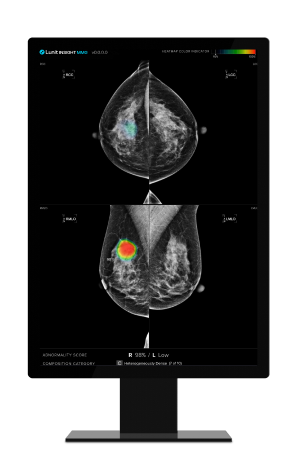

▲ Lunit's AI-powered mammography analysis solution 'Lunit INSIGHT MMG'

[SEOUL, South Korea, September 13, 2023] Lunit (KRX:328130.KQ), a leading provider of AI-powered solutions for cancer diagnostics and therapeutics, has unveiled the results of a collaborative study with Dr. Yan Chen, Ph.D., professor of digital screening at the University of Nottingham, United Kingdom. The study, recently published in Radiology, demonstrates that Lunit's AI-powered mammography analysis solution, Lunit INSIGHT MMG, matches the diagnostic performance of human readers. The study, which involved comparing Lunit's solution with assessments by 552 human readers, represents a significant milestone in the field of medical imaging and the future of breast cancer detection.